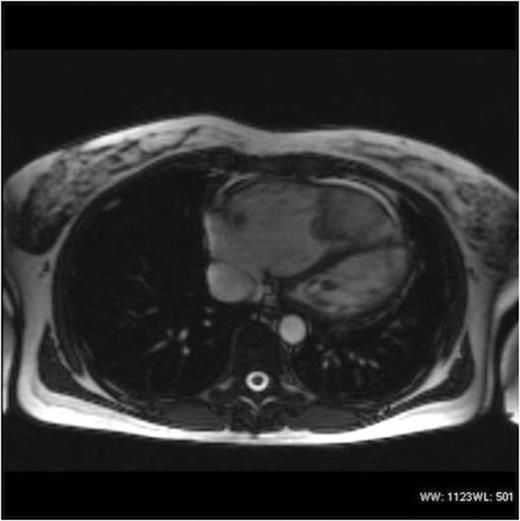

Echocardiography revealed a very large lobulated heterogenous mass in the right ventricular apex. A further mass or extension of this was also seen in the right ventricular outflow tract. This extension was mobile and had a homogenous texture. MRI and CT Thorax (Figures 1 & 2) demonstrated a 4.1cm x 9cm x 4.1cm lobulated mass within the right ventricle, obstructing the right ventricular outflow tract.